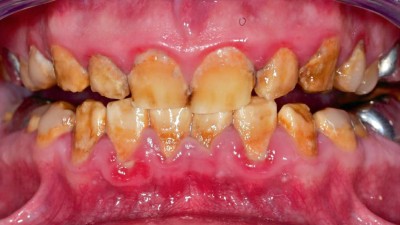

Die Assoziation von Parodontitis und rheumatoider Arthritis

Parodontitis (PAR) und rheumatoide Arthritis (RA) gehören zu den häufigsten chronisch entzündlichen Erkrankungen des Menschen. In diesem Fortbildungsbeitrag beschreiben wir Ätiologie, Diagnostik, Klassifikation und Therapie der RA und klären über die Assoziation zwischen RA und PAR und deren Pathomechanismen auf. Somit sind Sie in der Lage, im Sinne eines interdisziplinären, präventiv ausgerichteten Behandlungsansatz die RA bei der zahnärztlichen Behandlung zu berücksichtigen.